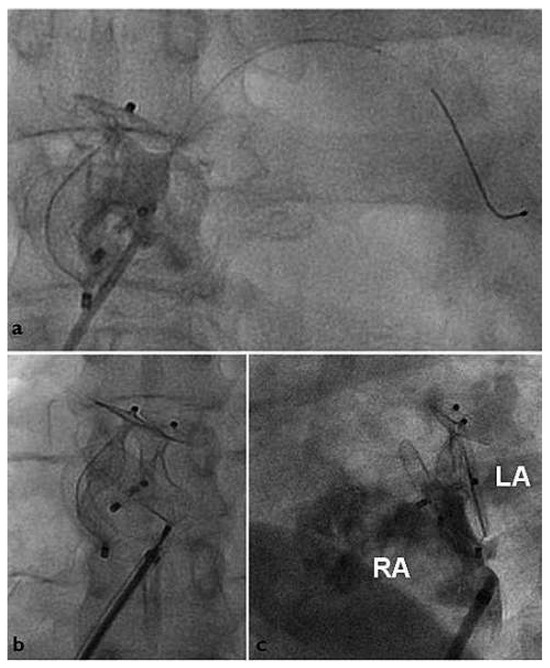

Triple Percutaneous Patent Foramen Ovale Closure

by Fabien Praz, Andreas Wahl and Bernhard Meier

Percutaneous patent foramen ovale (PFO) closure is mainly performed for secondary prevention of presumed paradoxical embolism. Since a residual shunt has been associated with recurrent events, complete PFO closure is desirable. We report the first case of ultimately successful percutaneous PFO closure using [...] Read more.

Percutaneous patent foramen ovale (PFO) closure is mainly performed for secondary prevention of presumed paradoxical embolism. Since a residual shunt has been associated with recurrent events, complete PFO closure is desirable. We report the first case of ultimately successful percutaneous PFO closure using successively 3 Amplatzer PFO devices. Full article

Show Figures

Figure 1